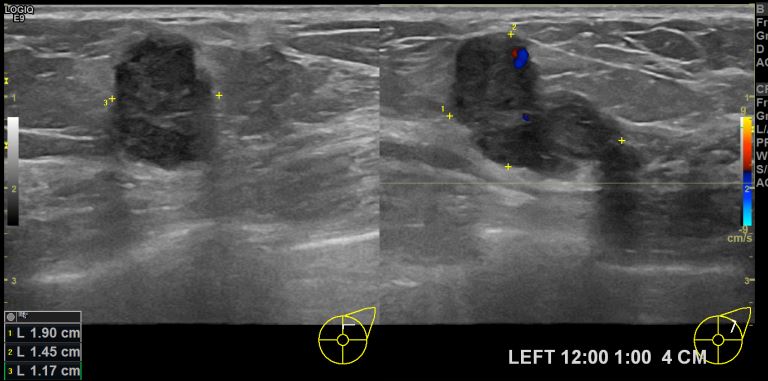

상기환자 좌측의 멍울로 내원하신 70대 여성분으로 본원 초음파상 좌측 12시에서1시 방향에서 4cm 떨어진 거리의 의심스러운 멍울 조직검사 시행하여 좌측 침윤성 유관암 진단되었습니다.